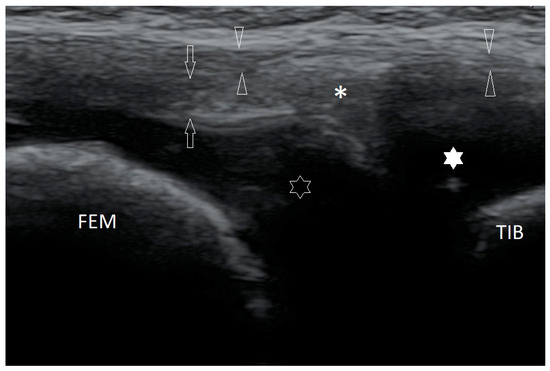

Basic Differences and Most Common Findings in Ultrasound Examinations of Musculoskeletal System in Children: A Narrative Literature Review

by Tomasz Poboży, Wojciech Konarski, Karolina Piotrowska-Lis, Julia Domańska, Kamil Poboży and Maciej Kielar

We present basic differences in the musculoskeletal ultrasound examinations between adults and children. Examiners who deal with adults on a daily basis have shared concerns about examining children. Such concerns may arise from the different approach to child ultrasounds, but they also come [...] Read more.

We present basic differences in the musculoskeletal ultrasound examinations between adults and children. Examiners who deal with adults on a daily basis have shared concerns about examining children. Such concerns may arise from the different approach to child ultrasounds, but they also come from differences in anatomical characteristics according to developmental age. We discuss the presence of growth plates, as well as non-mineralized parts of the bones. We also refer to the pathologies most often found in ultrasounds in early developmental stages. In the PubMed database, the set of keywords: “msk ultrasound in children”, “pediatric msk sonoanatomy”, “coxitis fugax”, “pediatric Baker’s cyst”, “Baker’s cyst ultrasonography”, “bone septic necrosis in ultrasonography”, “ultrasonography in juvenile idiopathic arthritis”, and “ultrasonography in juvenile spondyloarthropathies”, was used to identify a total of 1657 results, from which 54 was selected to be included in the article. We discuss the problem of osteochondritis dissecans, Osgood-Schlatter disease, examples of ligament injuries (especially in relation to the knee and ankle joints), exfoliation of growth cartilages, osteochondroma, exudates and inflammations affecting joints, and Baker’s cysts. In this way, we have collected useful information about the most common diseases of the musculoskeletal system in children. Full article